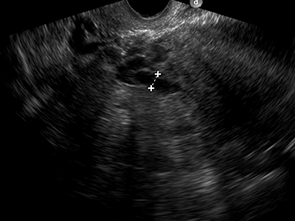

Fig. 2: a) Examen ecográfico por vía transvaginal, que muestra vena ovárica izquierda ectásica de 7.5 mm. b) Examen ecográfico por vía transvaginal, demostrando vena ovárica derecha normal, de 2.5 mm.

Hallazgos imagenológicos. En el eco Doppler ginecológico por vía transvaginal se observa varicocele pelviano (Fig. 1). La vena ovárica derecha mide 3.8 mm, y la izquierda, ectásica, 7.4 mm (Fig. 2). En el eco Doppler abdominal se visualiza la vena renal izquierda, de 3.1 mm en topografía del compás aorto-mesentérico y 8.1 mm en el segmento proximal al riñón izquierdo, con una velocidad 50cm/s en el compas y 30cm/s en el segmento proximal al riñón. El estudio corresponde en primera instancia a un síndrome de Nutcracker (Fig. 3).